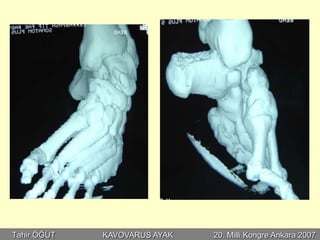

•Perkütan aşiloplasti

•Plantar fasya gevşetme

•Peroneus longus transferi

•Kalkaneal osteotomi

•1. Metatars osteotomisi